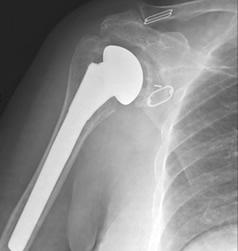

A differenza della protesi anatomica tradizionale, la protesi “inversa” inverte la normale anatomia della spalla.

Nella protesi inversa: la “palla” viene fissata alla scapola e la “coppa” all’omero.

Questa inversione meccanica permette al muscolo deltoide di sollevare il braccio anche quando i tendini della cuffia dei rotatori sono completamente rotti o assenti.